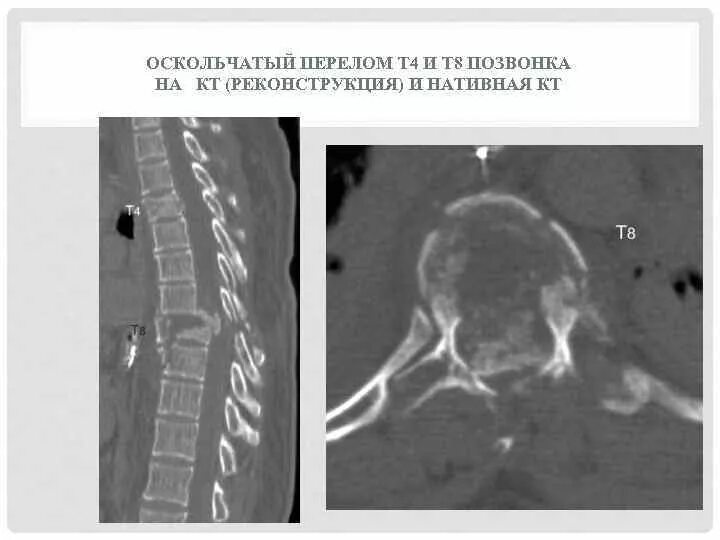

Перелом грудного позвонка код